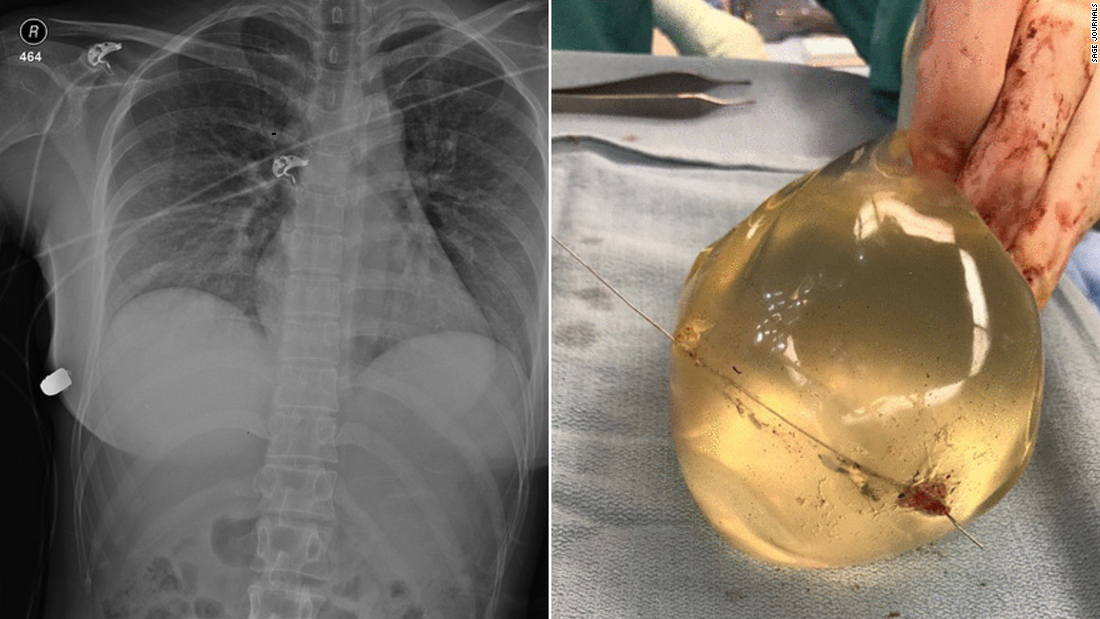

Woman's Breast Implant Deflects Bullet, Saving Her Life – CNN

www.cnn.com

implant implants deflects doctors womans tue sage